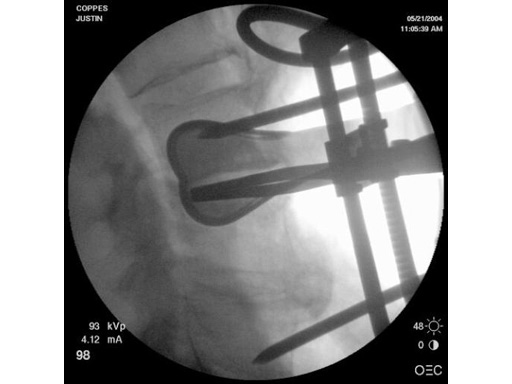

With the introduction of the SynFrame Standard Access and Retractor System, anterior mini-open procedures and less-invasive spine surgery became attainable for many surgeons. The SynFrame Standard Access and Retractor System enables small incisions and significantly reduces tissue damage and blood loss. In anterior lumbar procedures, both fusion and disc arthroplasty, improved intraoperative fluoroscopic visibility is needed. In disc arthroplasty good visualization is especially important. The radiolucent retractor blades offer surgeons a wider range of options for patients with excessive soft tissue and varying patient anatomy and provides improved fluoroscopic visualization. They are available in 80200 mm lengths in the standard 25 mm width and wide 50 mm width. The black surface coating also helps to reduce glare from the instruments during surgery.